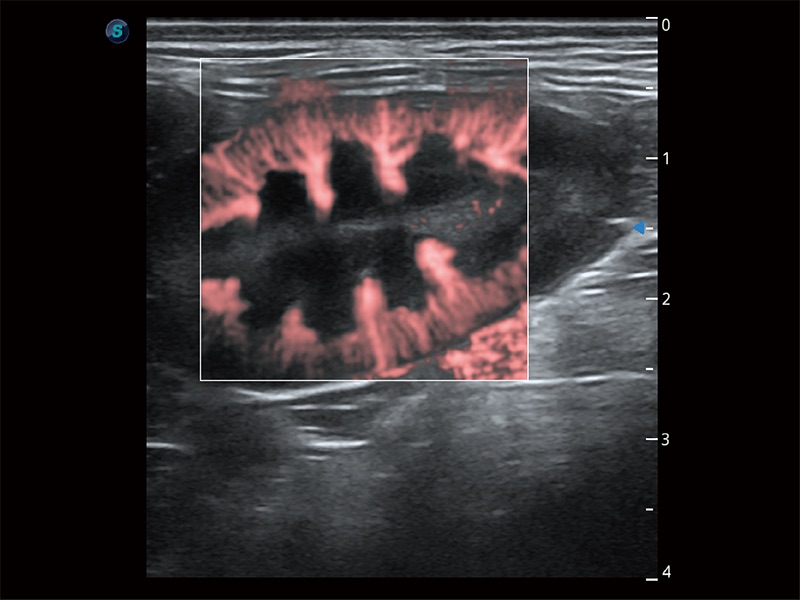

在傳統(tǒng)二維血流成像的基礎(chǔ)上,呈現(xiàn)血流的立體感,具有動(dòng)感的生命力之美。即便是微小的血管也能輕松應(yīng)對(duì),提高了血流的視覺敏感性。